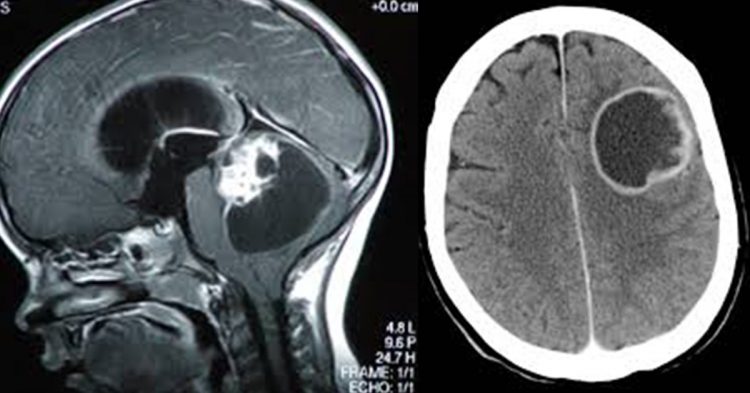

L’agghiacciante testimonianza di Pierandrea, figlio della famiglia Marzola svegliatasi all’alba con il cuore spezzato è “come un pugno a in mezzo al petto“. Il primogenito della famiglia di Cadoneghe era titolare di un punto vendita sportivo in città. Il soccorso immediato in ospedale è risultato invano e fuori tempo massimo. La madre di famiglia, la signora Maria Teresa, conosciuta nel quartiere con il nomignolo Tea non è riuscita a vincere il tumore. Nel tentativo disperato di capire i motivi che avevano stroncato la sua vita, le verità sono state portate alla luce dalla dottoressa di Tea tra gli occhi increduli del figlio. La signora Tea, 77enne di Cadoneghe in provincia di Padova, soffriva da tempo di disturbi alla cervicale, ma la diagnosi era riconducibile a fastidii dovuti alla terza età.

La dottoressa del nosocomio padovano indignata per non aver dichiarato i motivi dello stato di salute di Tea, ha ammonito il figlio. Ma alla luce dei fatti, non potendo appellarsi alla verità, Pierandrea, ignaro di tutto, cercava le risposte proprio dal medico. Ed ecco che lo shock prendere il sopravvento quando la dottoressa elenca i motivi che hanno avuto ragione della signora Tea. Il bollettino recitato, gettava nello sconforto più totale il figlio davanti a termini come metastasi ai polmoni e bernoccolo tumorale che le usciva dal seno.

Pierandrea sottolinea la forza di vivere della madre sul letto dell’ospedale. Il suo grido alla vita era testimonianza di una donna positiva e coraggiosa. Prima di chiudere gli occhi conversava con i medici dicendo che si sentiva alla grande. Ma il tumore abitava in Tea da almeno 5 anni.